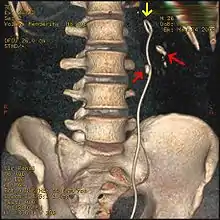

Three-dimensional reconstructed CT scan image of a ureteral stent in the left kidney (indicated by yellow arrow), with a kidney stone in the inferior renal pelvis (highest red arrow) and one in the ureter beside the stent (lower red arrow)